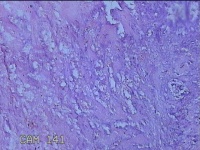

阑尾

临床诊断

急性坏疽性阑尾炎 弥漫性腹膜炎

一般病史

转移性右下腹疼痛3天。

标本名称

大体所见

灰白暗红色阑尾2.5x0.8x0.3cm一条,表面糜烂,肿胀,带大量系膜,部分已切开,见腔内暗红色,另有灰褐色粪石1.9x0.7x0.3m一枚。